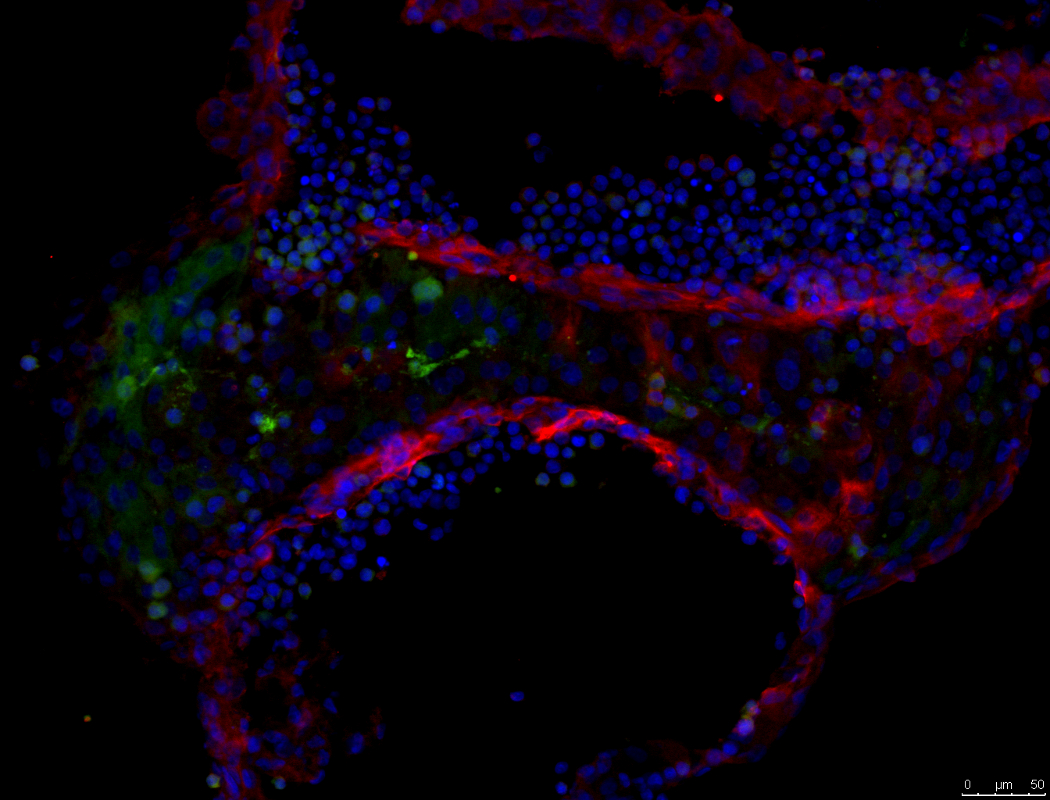

My mini-brain under the microscope.

My skin cells (fibroblasts) growing in a petri dish (in vitro) from a piece of skin tissue taken from my arm.